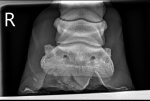

X-rays showed nothing too concerning, thankfully. No sinking, 6degrees rotation on bad foot and 4 on other, but given how sore she is, vet was very relieved and prognosis is good.